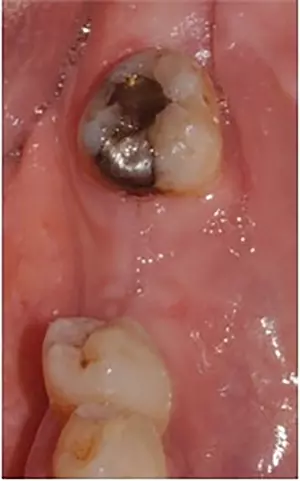

Eine 53-jährige gesunde Patientin stellte sich in unserer Klinik zur prothetischen Rehabilitation bei Vorliegen einer bilateralen Schaltlücke bei fehlenden Zähnen 37 und 36 vor. Zum Zeitpunkt der Erstvorstellung zeigte sich ein prothetisch und konservativ insuffizient versorgtes Gebiss mit einer Freiendsituation in regio 17 und 16 sowie Schaltlücken in den Regionen 37 und 36 sowie 46 und 47 (Abb. 1). Zur Beurteilung der radiologischen Ausgangssituation wurde präoperativ eine Digitale Volumentomographie angefertigt.